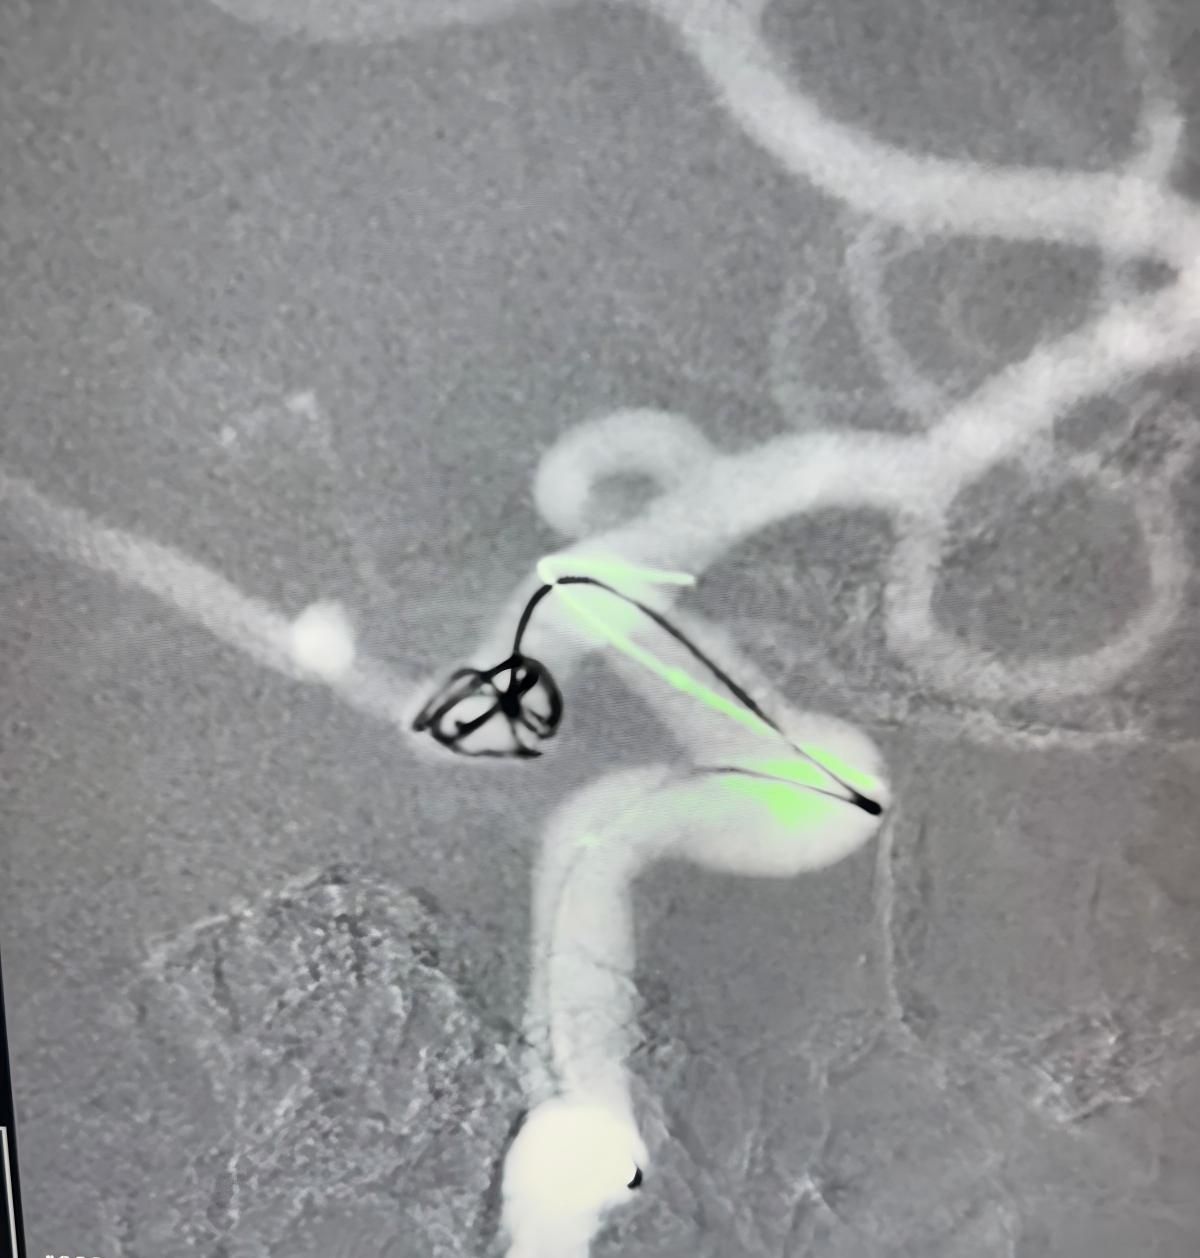

Tedavi nuva kullanıldı®Akış değiştirici (TJED-D 5.0-14), daha yoğun®3d bobin ve frepass®Posterior iletişim arter anevrizması için microcatheter (tjmc18 plus).

Dr. mutis, cihazın mükemmel görünürlüğünü vurguladı ve alınmanın pürüzsüz olduğunu kaydetti. Son sonuçtan büyük memnuniyeti dile getirdi.